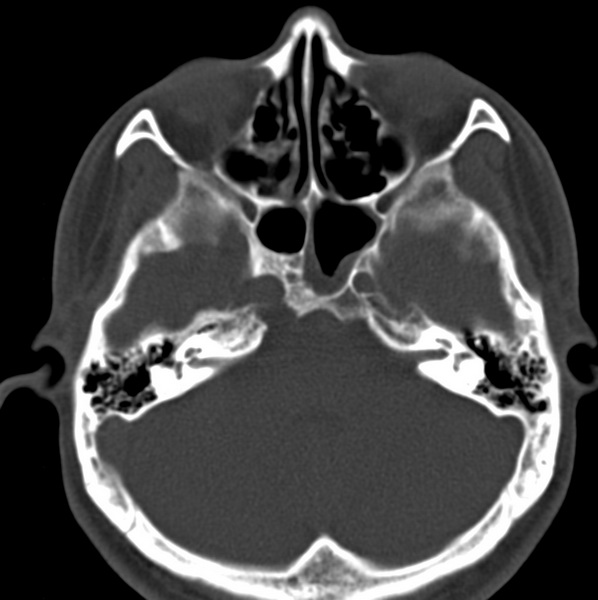

男、31、鼻咽部肿瘤放疗后请帮忙看看。

效果好,右侧破裂孔扩大,局部骨质缺损,为颅底骨质破坏。

1)鼻咽部肿瘤侵犯颅底放疗术后改变。2)左侧蝶窦炎。

咽后壁增厚,左侧咽鼓管隆突增大、咽鼓管咽口变浅,同侧咽旁间隙较窄。右侧颅底骨质破坏?为什么不在同一侧?

鼻咽部肿瘤侵犯颅底放疗术后改变.